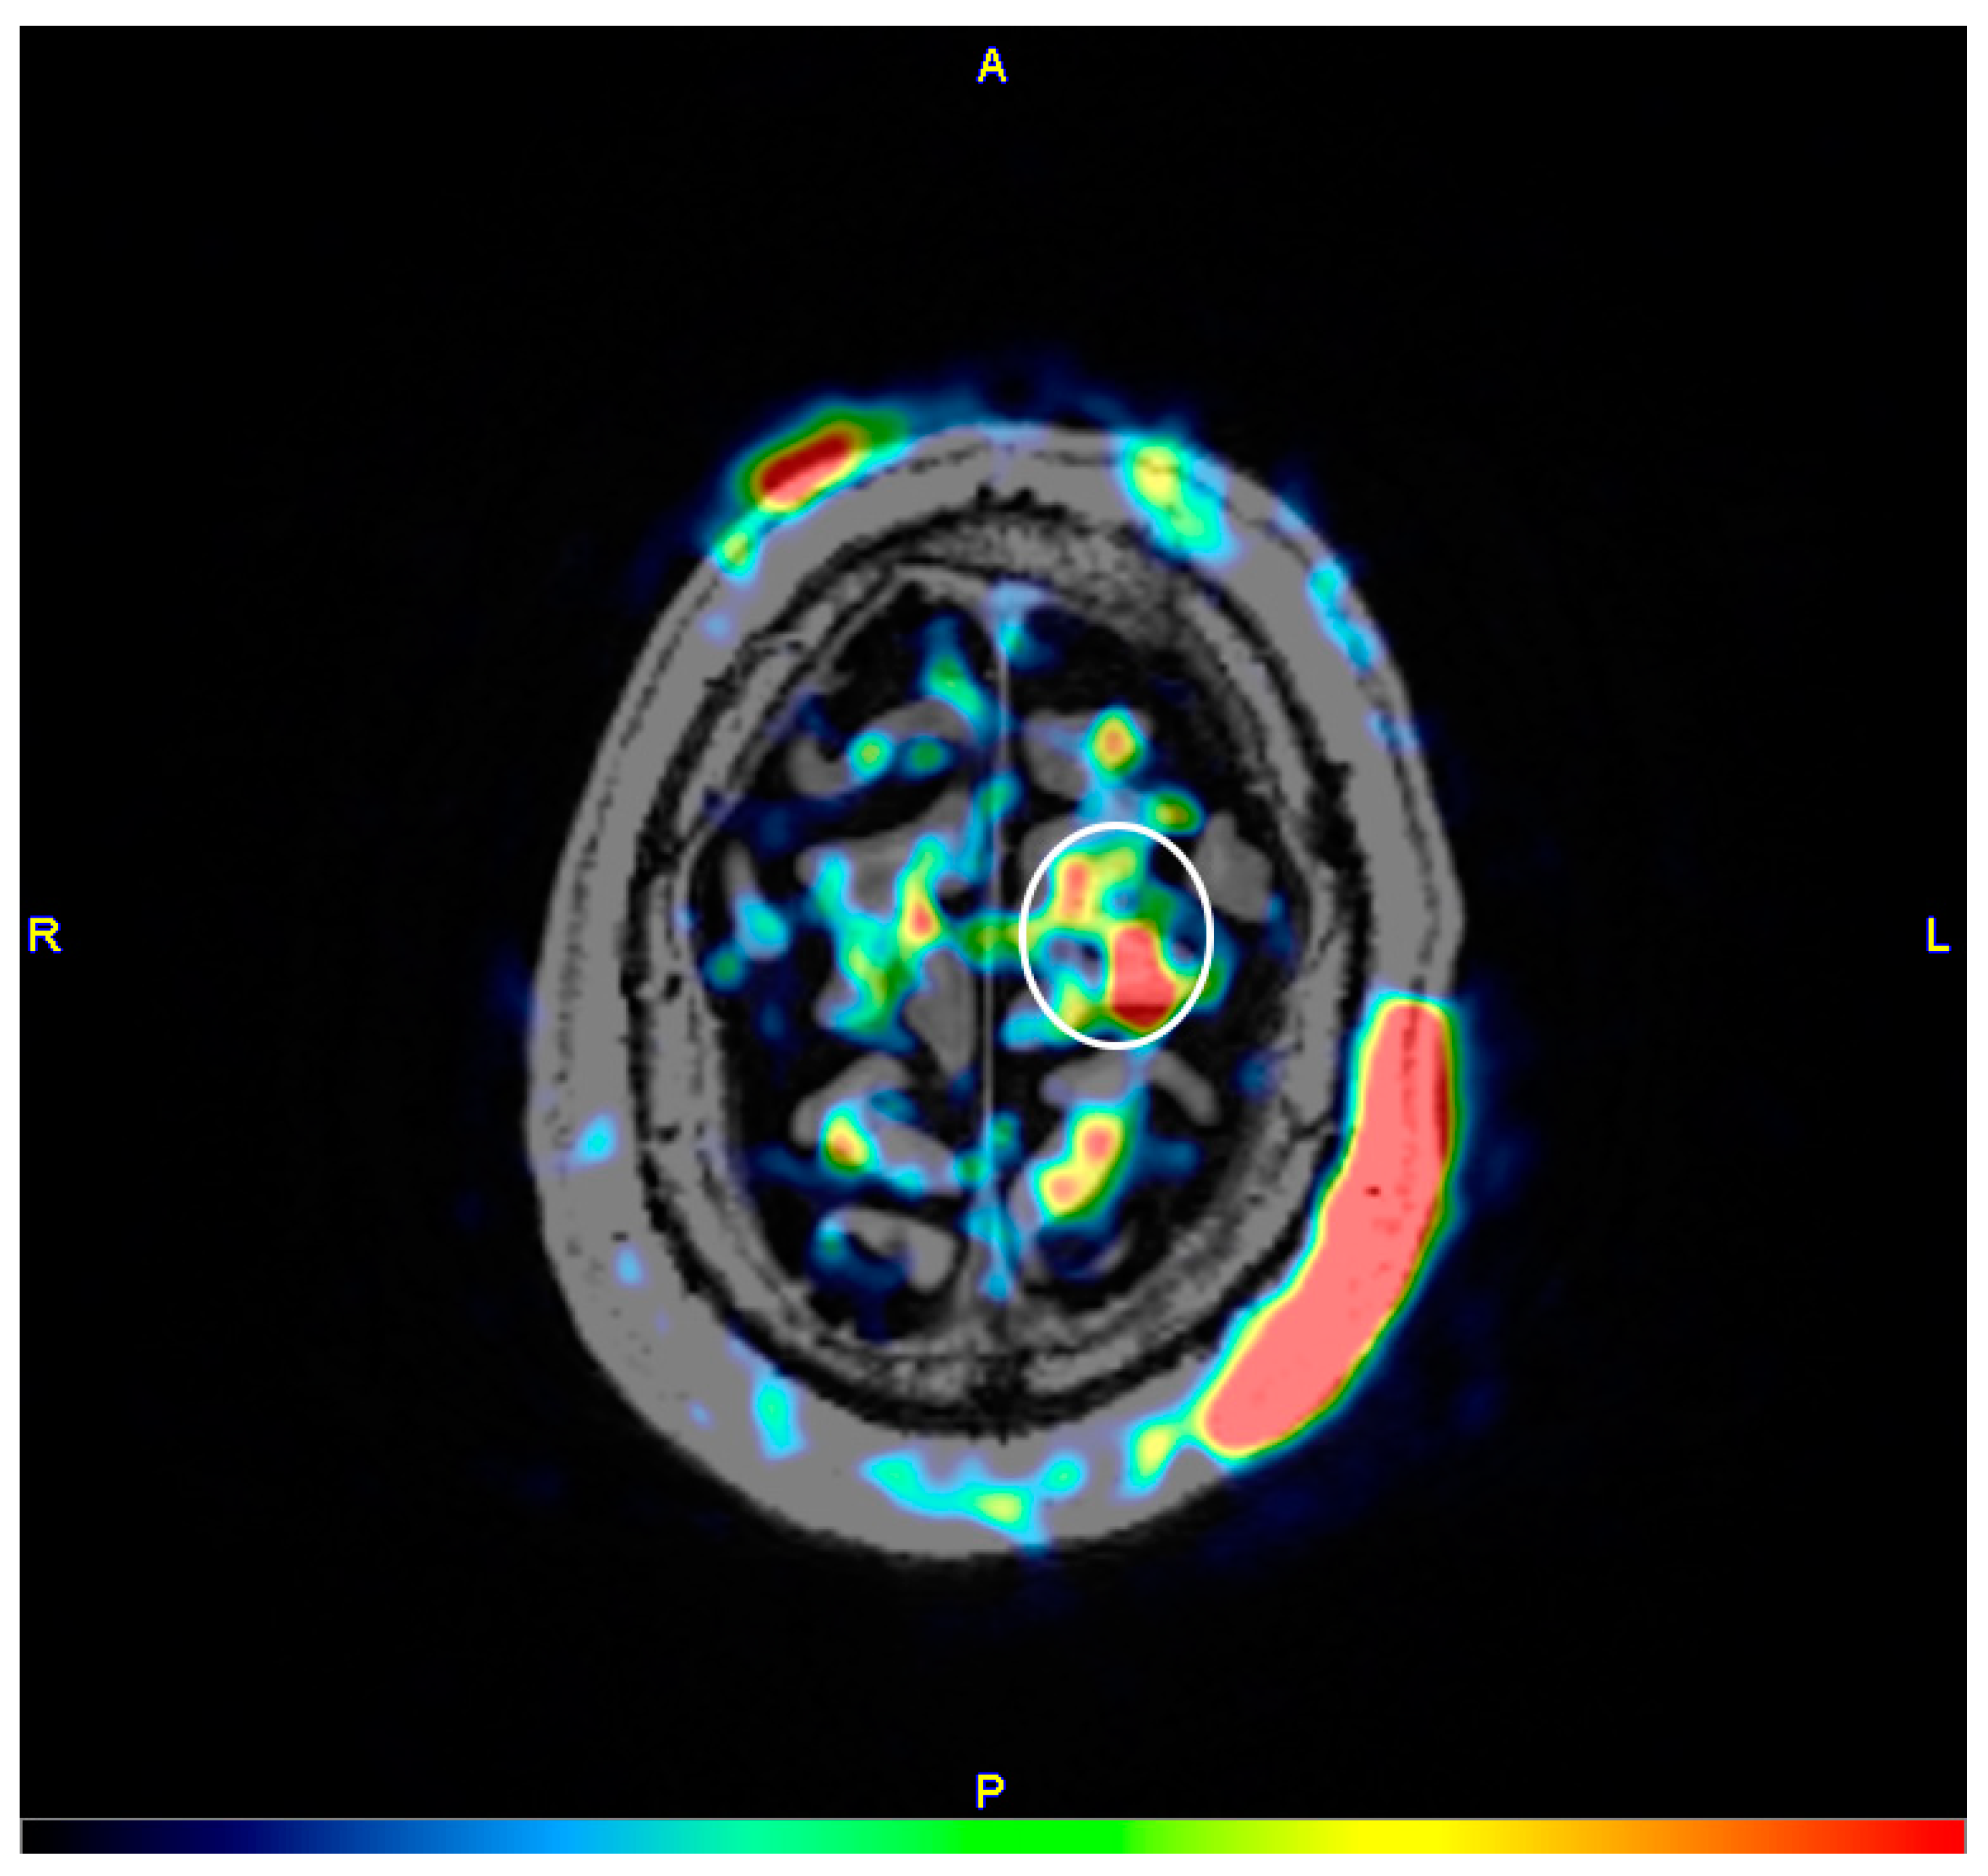

2. Materials and Methods

3. Results

3.1. Experiment 1, Dorsolateral Prefrontal Cortex

3.2. Experiment 2, Primary Motor Cortex